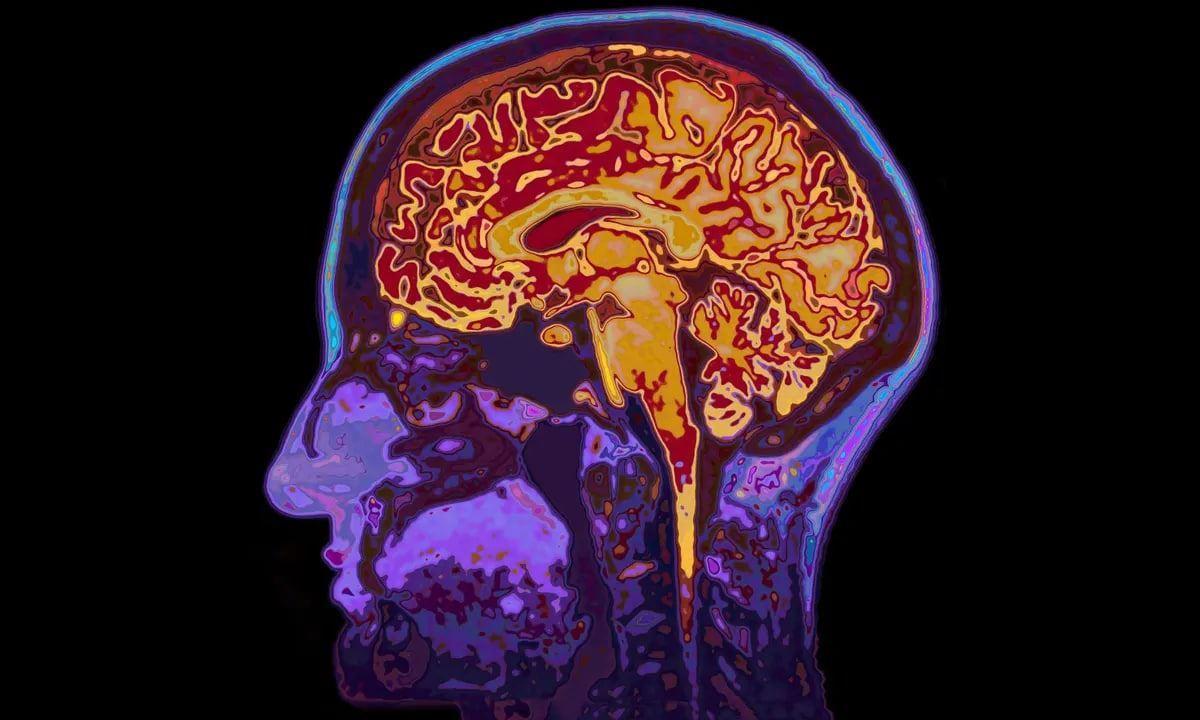

محققان در مطالعات جدید خود نشان داده‌اند که انزوای اجتماعی باعث ایجاد تغییراتی در ساختار مغز و شناخت انسان‌ها می‌شود و حتی خطر ابتلا به زوال عقل را در افراد مسن افزایش می‌دهد.

هرچند تاکنون آزمایش‌هایی در این زمینه انجام شده، اما محققان این بار تلاش کرده‌اند تا نحوه تاثیر انزوای اجتماعی بر ماده خاکستری مغز را با دقت بیشتری بررسی کنند. آن‌ها برای رسیدن به اهداف خود، داده‌های نزدیک به 500 هزار نفر از بانک اطلاعات پزشکی (Biobank) بریتانیا را با میانگین سنی 57 سال بررسی کردند. همچنین در این تحقیق از عکس MRI حدود 32 هزار نفر استفاده شد.

به گفته آن‌ها، افراد منزوی نسبت به سایر افراد قدرت درک ضعیف‌تری دارند که شامل حافظه و زمان واکنش می‌شود. همچنین در برخی قسمت‌های مغز آن‌ها مانند لوب گیجگاهی (مسئول پردازش صدا)، لوب پیشانی (توجه، برنامه‌ریزی و وظایف شناختی پیچیده) و هیپوکامپ حجم کمتری از ماده خاکستری دیده می‌شود.

هیپوکامپ یک ناحیه کلیدی از مغز انسان‌ها است که در یادگیری و حافظه نقش مهمی دارد و معمولا یکی از اولین بخش‌هایی است که در شکل‌گیری بیماری آلزایمر مختل می‌شود.